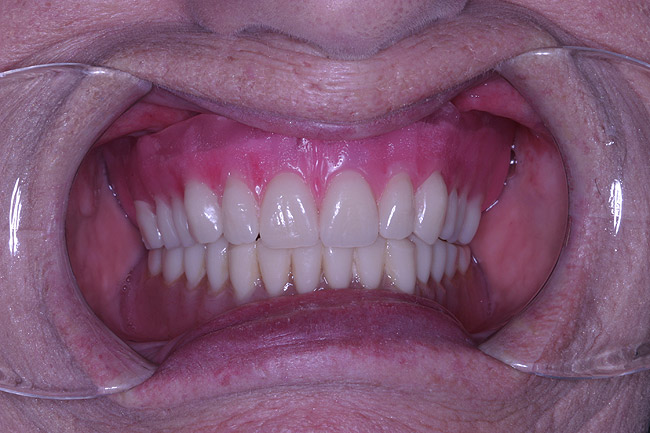

The laboratory then fabricated a light-cured, stabilized base plate on which anterior and posterior teeth were set using the silicone putty mold made previously and waxed up to final contour and delivered to the office. The upper denture was tried in and a visual examination was performed to certify function, esthetics, phonetics, and patient/clinician satisfaction (Figure 14). The denture was sent back to the laboratory for final processing with the Ivocap Denture System (Ivoclar Vivadent North America, Amherst, NY). The prosthesis was trimmed and polished to high luster to prepare for final insertion (Figure 15). Additionally, Massachusetts requires denture labeling with a patient identifier (wearer's name, driver's license number, or Social Security Number, etc) for forensic purposes, and this was exacted according to state law.28

Figure 14  Retracted view of try-in.

Figure 14

Figure 15  Final case, postoperative.

Figure 15